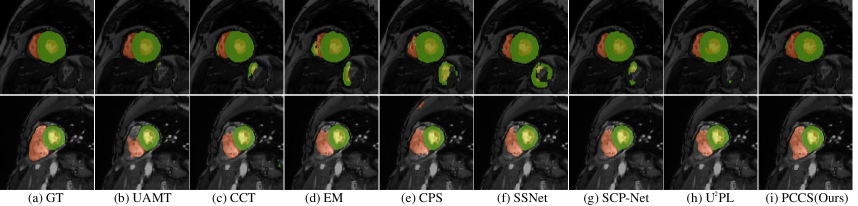

Results of Comparison Methods on ACDC. Table 6 shows the experimental results of the proposed PCCS on the ACDC when using 10% labeled data and 90% unlabeled data. In particular, for Dice, PCCS achieves 85.07%, 84.03%, and 90.04% in RV, Myo, and LV, respectively. PCCS excels in Myo and LV, while being slightly lower in RV compared to U2PL (86.07%). For 95HD, PCCS remains competitive across all classes. In summary, Table 6 indicates that while other methods perform well only in a single class, PCCS performs well across multiple classes. Therefore, PCCS outperforms other methods in average performance.

Comparison on Visualization on ACDC. Fig. 9 shows some visualization results on different methods when using 10% labeled images on the ACDC dataset. We choose four representative methods to show the superior performance of PCCS. Not only is the prediction performance of PCCS significantly higher than SSNet, SCP-Net, U2PL, but also the visualization results are closer to the ground truth label with fewer missing and unexpected regions.